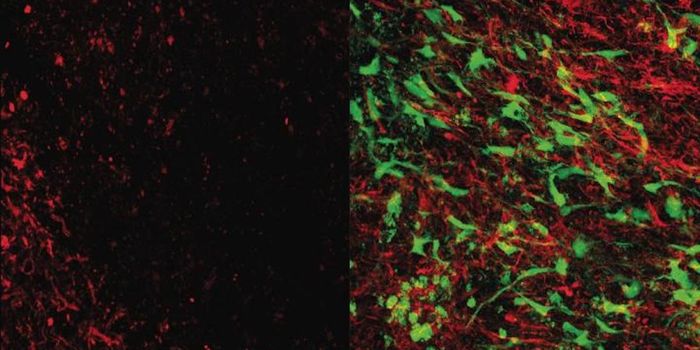

JAN 07, 2019NeuroscienceResearchers from the Texas A&M College of Medicine, demonstrated that grafting of medial ganglionic eminence (MGE)-deriv ...